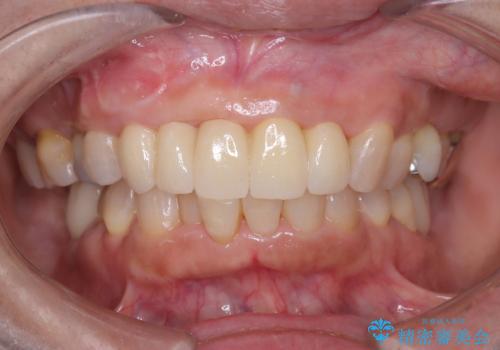

前歯の隙間とへこみが舌で触ると気になる|矯正治療は絶対にしたくない|抜歯即時インプラント+オールセラミッククラウンで審美修復

前歯の変色が気になる〈セラミッククラウン〉

担当医 瀧村怜未